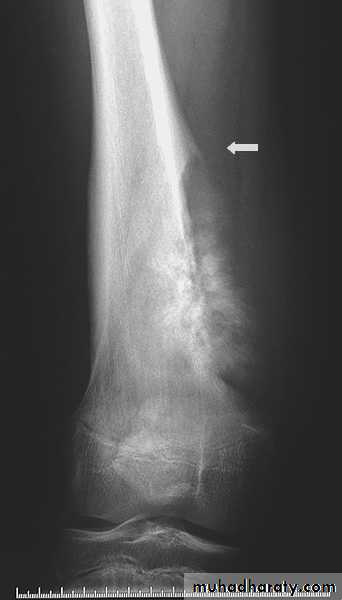

The sign & findingsWide zone of transition is being

Benign or malignant ????Codman's triangle

Elevation of the periosteum at the side of the tumor marginlytic, expansile lesion, Sub articular in location give the soap bubble appearance

Giant cell tumoronion peal periosteal reaction

Codman's triangle is a type of periosteal reaction seen with aggressive bone lesions could be singlelayer and mulitlayered periosteal reaction), only the edge of the raised periosteum will ossify.